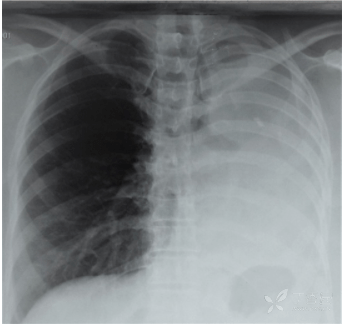

肺不张 肺实变,这些影像特征你当知!

查体:心率 98 bpm,r 26 cpm,左胸凝集综合征,这个可能是指左肺实变

教科书上也很少见这么经典的胸片附肺实变的轮廓征图

6969图 1 为患者 8 月 19 日胸片,提示右下肺实变阴影6969

儿童肺部实变的影像表现和分析